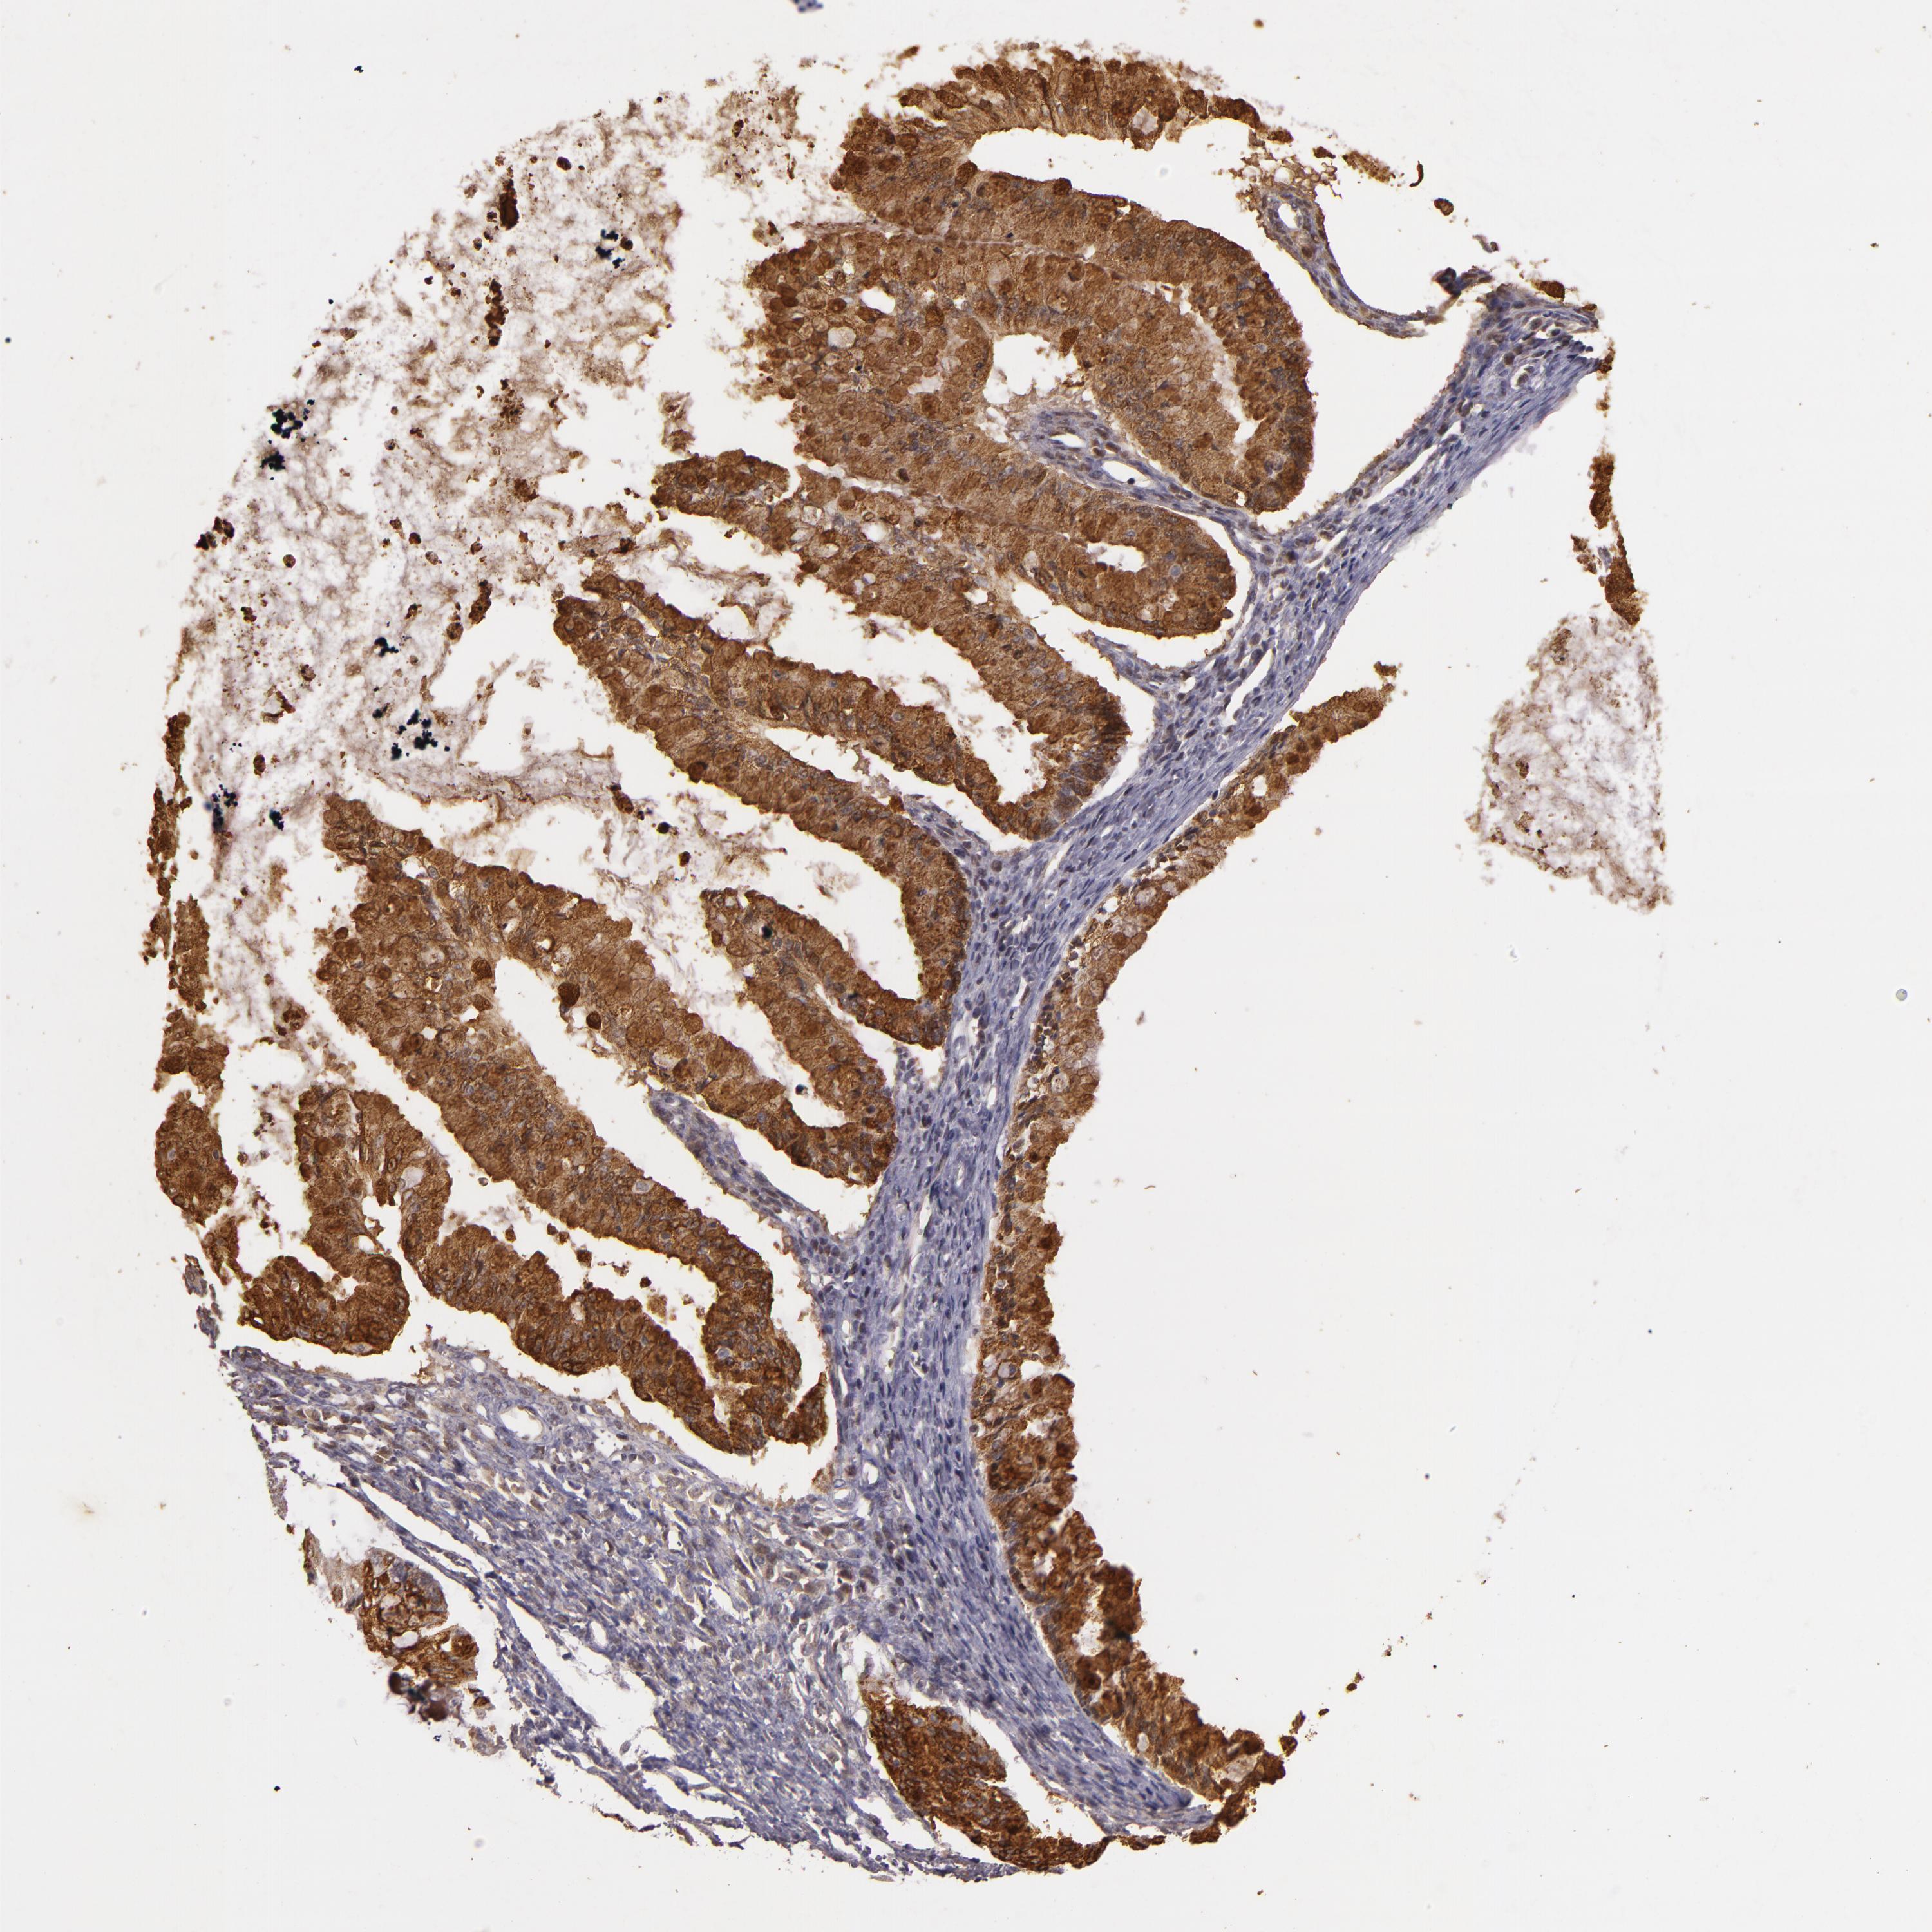

OVARIAN CANCER - Protein expressioni

A mouse-over function shows sample information and annotation data. Click on an image to view it in a full screen mode. Samples can be filtered based on level of antibody staining by selecting one or several of the following categories: high, medium, low and not detected. The assay and annotation is described here.

Note that samples used for immunohistochemistry by the Human Protein Atlas do not correspond to samples in the TCGA dataset.

Antibody stainingi

Antibody staining in the annotated cell types in the current human tissue is reported as not detected, low, medium, or high, based on conventional immunohistochemistry profiling in selected tissues. This score is based on the combination of the staining intensity and fraction of stained cells.

Each image is clickable and will lead to virtual microscopy that enables deeper exploration of all samples and also displays staining intensity scores, fraction scores and subcellular localization as well as patient and tissue information for each sample.

Antibody HPA003425

Antibody CAB002170

Cystadenocarcinoma, serous, NOS

Cystadenocarcinoma, mucinous, NOS

Carcinoma, endometroid